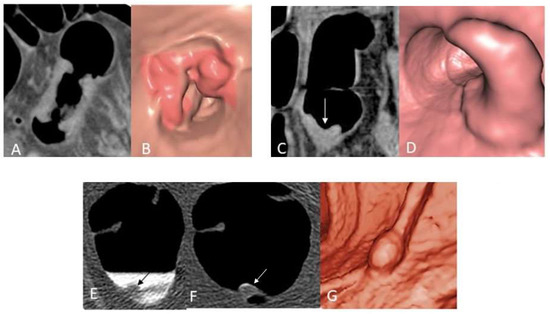

- Ricci, Z.J.; Mazzariol, F.S.; Kobi, M.; Flusberg, M.; Moses, M.; Yee, J. CT Colonography: Improving Interpretive Skill by Avoiding Pitfalls. Radiographics 2020, 40, 98–119. [Google Scholar] [CrossRef]

- Zalis, M.E.; Barish, M.A.; Choi, J.R.; Dachman, A.H.; Fenlon, H.M.; Ferrucci, J.T.; Glick, S.N.; Laghi, A.; Macari, M.; McFarland, E.G.; et al. CT colonography reporting and data system: A consensus proposal. Radiology 2005, 236, 3–9. [Google Scholar] [CrossRef]